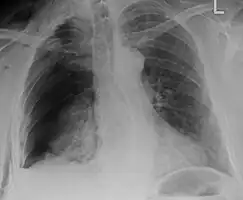

| An X ray showing multiple old fractured ribs of the person's left side as marked by the oval. | |